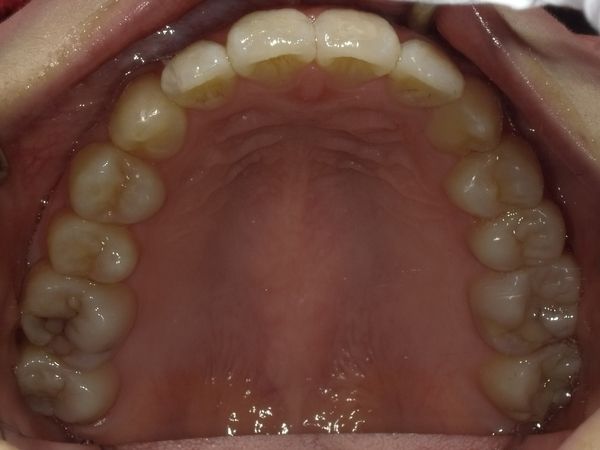

ガタガタとした歯並びや八重歯(叢生)CASE68